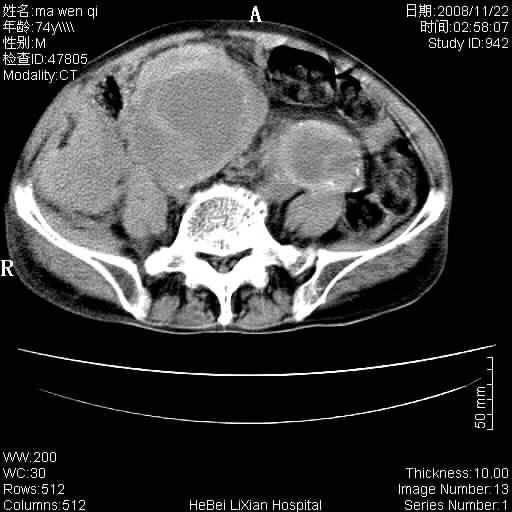

患者男 74岁.突然昏迷,休克6小时.血压70/30,头颅ct未见异常,既往体健.

补充病史,保留导尿10小时,尿袋内只有少许尿液,患者于住院后15小时后去世.

腹主动脉、双侧髂动脉夹层动脉瘤破裂出血进入腹腔。

1)考虑双侧髂动脉瘤并右侧动脉瘤破裂出血,右侧腹膜后及腹腔积血。2)双侧腹股沟疝。

1)考虑,腹主动脉、双侧髂动脉夹层动脉瘤破裂伴右侧腹膜后及腹腔积血。2)双侧腹股沟疝。